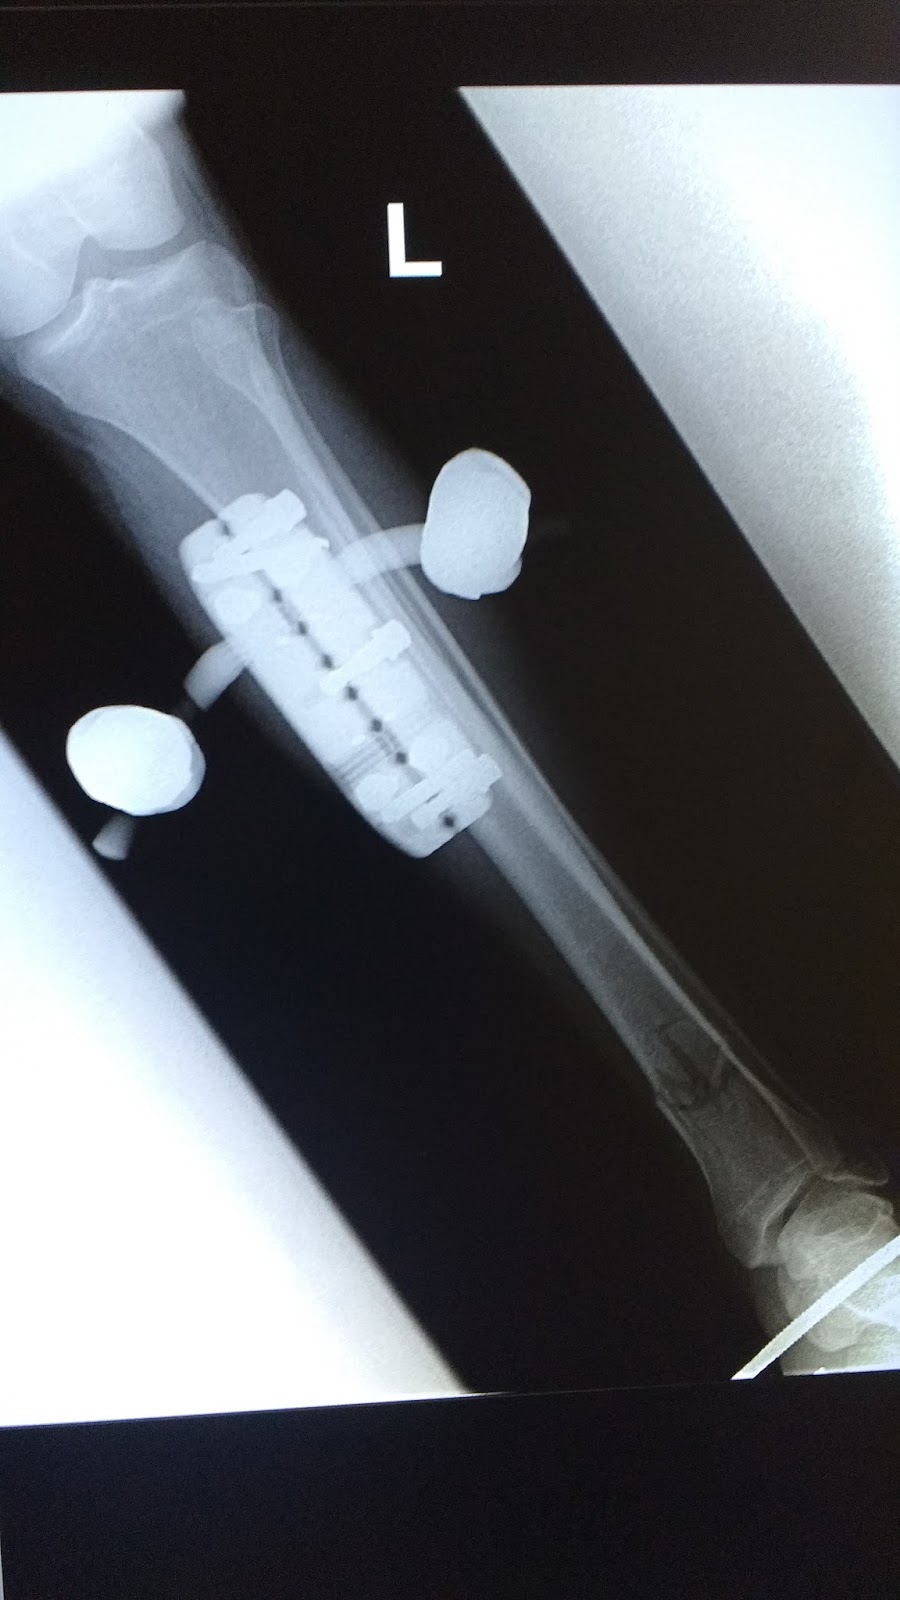

The rest of the night is lost to the labyrinth of trauma, but I know I had an MRI and a CAT scan. They told me I was lucky, and that it was almost a miracle that I’d only sustained injuries to my left leg. The leg in question, unfortunately, was in pieces, shattered like glass, and on top of that, my knee had cracked. It would need surgery, they said. They refused to give me any water, explain what surgery was needed, or introduce me to a doctor. I complained a lot. Andrew snuck me ice chips when my mouth got so dry it started frothing a little.

One surgery later, I was better in the sense that I was now partially a cyborg and also in excruciating pain.

I mean, I know I like Iron Man and all, but this is just ridiculous.

See below for a fun album of my bone being broken and then (sorta) fixed (well... stabilized, anyway) via an external fixator! (Warning: mild gore.)